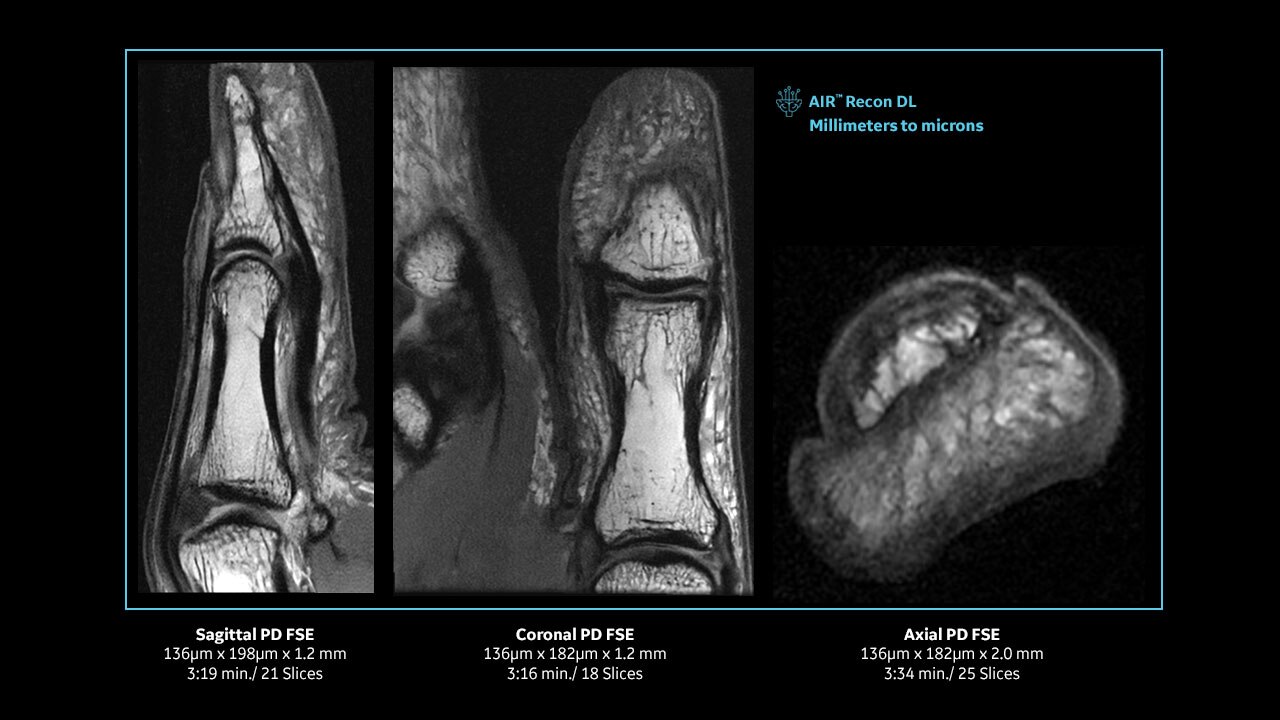

Achieve pin-sharp image quality with pioneering AIR™ Recon DL AI technology

With access to the latest advanced AI technology, you can scan all anatomies and achieve pin-sharp images. Our pioneering Deep Learning-based reconstruction algorithm AIR™ Recon DL accelerates scan time and puts patients at ease.